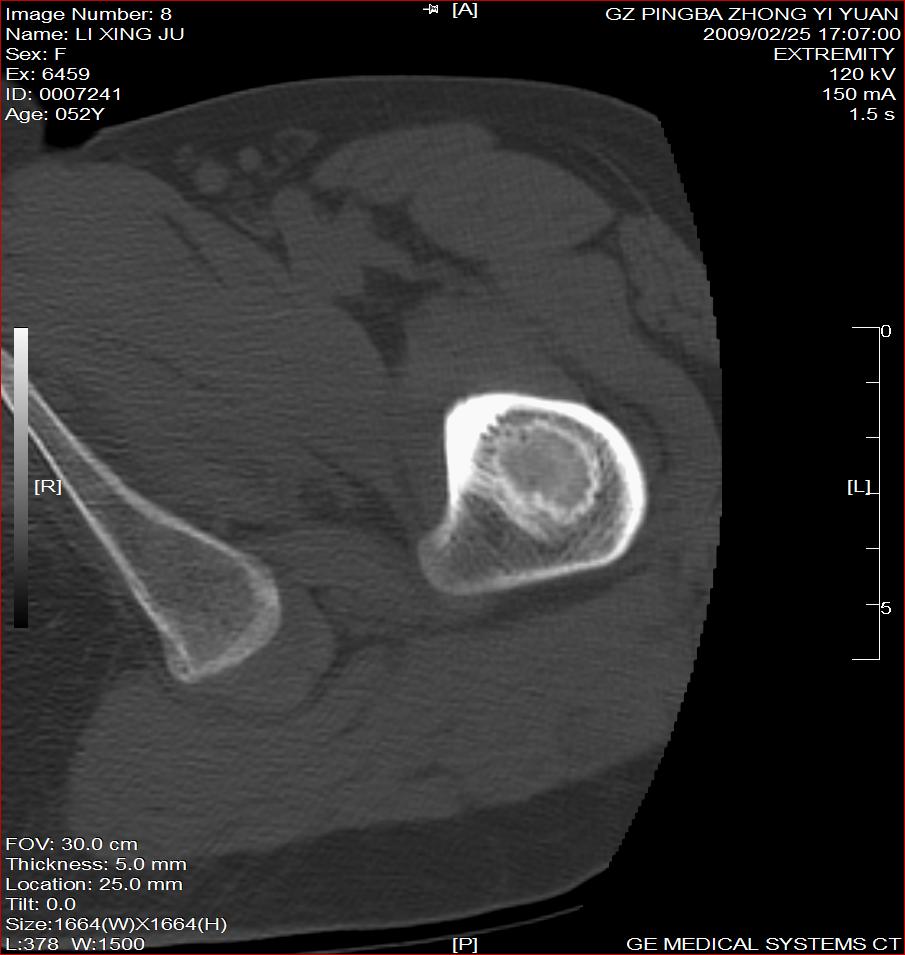

标题: CT18521:左大腿疼痛不适1+月 [打印本页]

标题: CT18521:左大腿疼痛不适1+月

考虑-----股骨骨化性纤维瘤可能性大,不除外---局限性骨纤

考虑:左股骨骨化性纤维瘤

考虑:骨纤或骨梗可能性大

考虑 左股骨骨化性纤维瘤。

骨梗塞

考虑骨化性纤维瘤可能性大